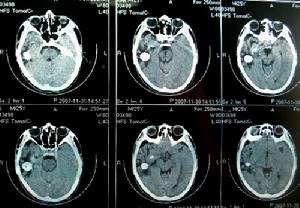

耳源性腦炎臨床表現

耳源性腦炎(二)可伴精神及神經症狀,如煩躁不安、抽搐,重者譫妄昏迷以及相關的顱神經麻痹等。

(一)腦膜刺激征,頸有抵抗菌素或頸項強直,甚者角弓反張克(Kerning)征及布魯金斯基(Brudzinskin)征陽性。

(二)腦脊液壓力增高、混濁,細胞數增多,以多形核白細胞為主,蛋白含量增高,糖含量降低,氯化物減少。細菌科研培養可為陽性。血中白細胞增多,多形核白細胞增加。

(一)在足量抗生素(青黴素、先鋒黴素、左氧氟沙星)及磺胺類藥物控制下行乳突探查根治術,清除病灶。對骨質破壞者,除去骨板至正常腦膜暴露。

(二)必要時,腰椎穿刺注入適量抗生素。

(三)注意支持療法及水和電解質平衡。